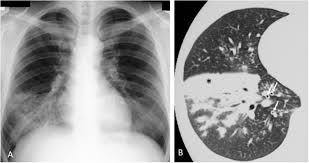

- 흉부 X-ray: 기관지 주위 침윤, 폐렴 소견